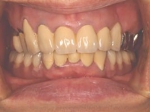

治療前治療前インセラム(オールセラミック)冠による修復。 主訴は前歯が汚い 金属を使わないオールセラミックでの治療を勧めた。 術前 治療後治療後術後

治療前治療前術前 治療後治療後術後 歯の尖端の透明感までよく再現できている。